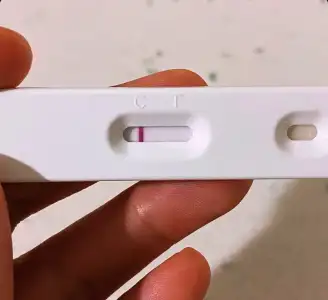

Hahahhaha öteki tarafa gel atcam ben sana test 5 gün sonraCanım test çekti test aşeriyorum. Bide bu ay umduğumdan erken geldi adet hiççç yapamadım canım sıkılıyor ellerim titriyor. Abla bana bir test ya noooollllluuuuurrr abla yaaa